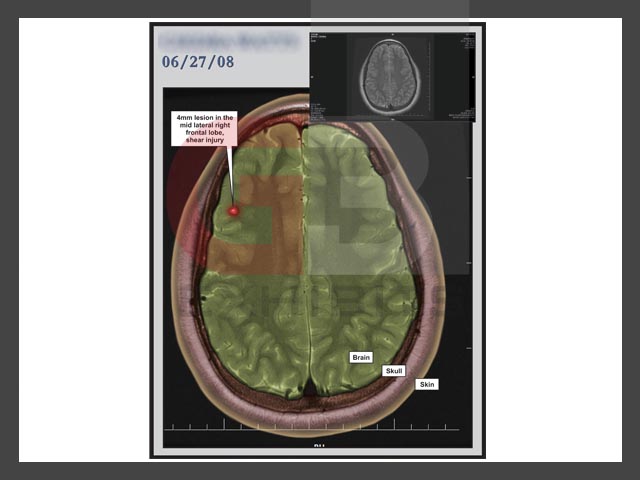

Click to enlarge: Neck Click to enlarge: Neck Click to enlarge: Brain Slice 1